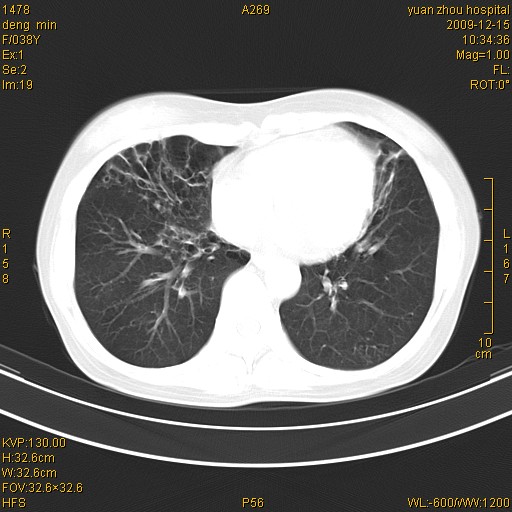

标题: CT23919:F38Y 咳嗽月余 [打印本页]

标题: CT23919:F38Y 咳嗽月余

支气管扩张。典型。

右肺中下叶、左肺上叶舌段及左肺下叶支气管扩张合并感染。